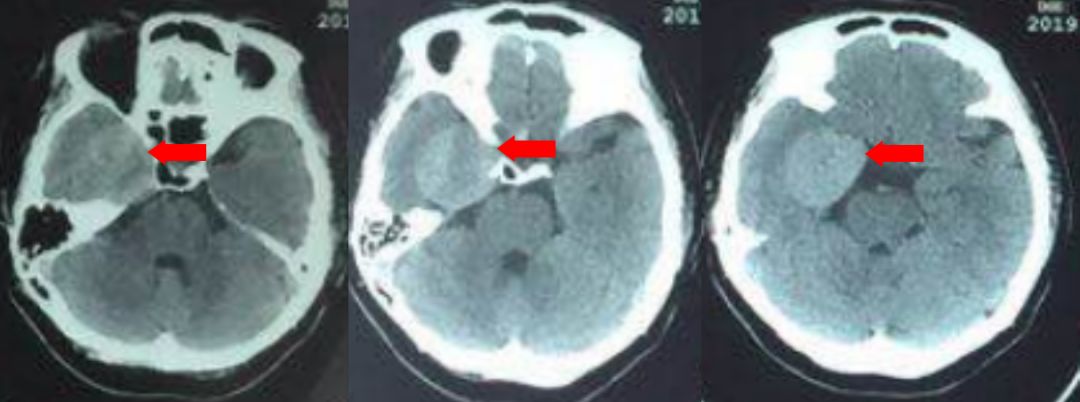

头CT:右侧海绵窦区可见类圆形高密度影,密度均匀,边缘较清晰,与正常组织界限清楚,考虑颅脑肿瘤可能性大。

术后复查头CT,颅内未见出血,中线居中,环池清楚。